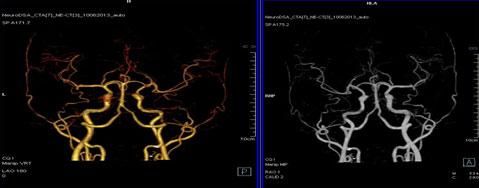

二、多層螺旋CT頭頸部及體部血管成像技術:

該機掃描覆蓋範圍廣、時間短,多種後處理分析軟件能顯示各血管細小分支,可以清晰顯示動脈瘤、動脈夾層、血管畸形、血管狹窄及動脈粥樣硬化斑塊等,适用于頭頸部血管成像、肺動脈成像、胸腹部血管成像及四肢血管成像。

1.顱腦血管成像:

動脈瘤